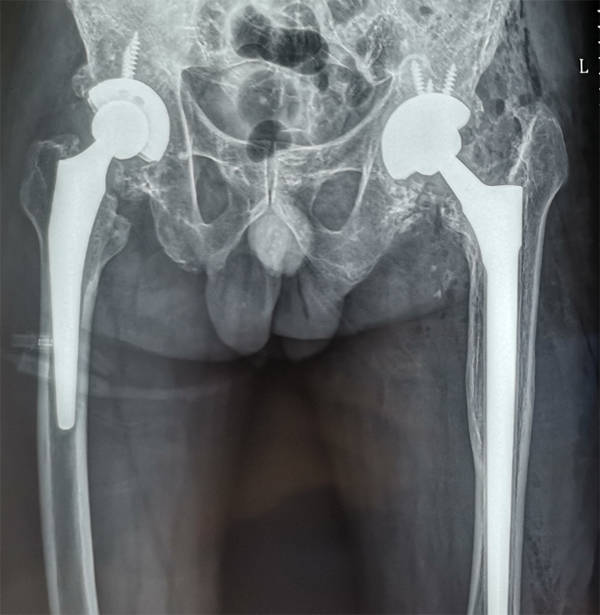

南昌大学第一附属医院完成一例高难度全髋关节翻修术

单县中心医院骨二科一例高难度人工全髋关节翻修术获成功